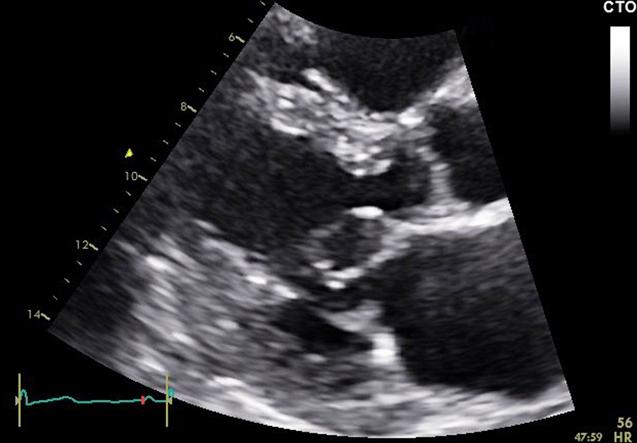

• Intracardiac blood cyst is a rare congenital abnormality that can be found in adults. • It is most commonly attached in the valves, particularly the mitral valve. • Echocardiography is the imaging modality of choice for the diagnosis of blood cyst. • Cardiac MRI contributes to the diagnosis, typically showing absence of cyst enhancement. • Conservative management is reasonable in the absence of effects on cardiac function.

• 超声心动图是诊断血囊肿的首选影像学检查方法。